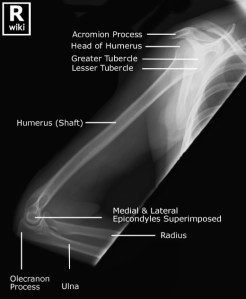

Above images from WikiRadiography (WetPaint) here.